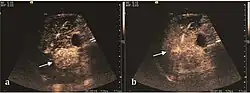

HCC appearance on 2D ultrasound is that of a solid tumor, with imprecise delineation, with heterogeneous structure, uni- or multilocular (encephaloid form). An "infiltrative" type is also described which is difficult to discriminate from liver nodular reconstruction in cirrhosis. Typically HCC invades liver vessels, primarily the portal veins but also the hepatic veins . Doppler examination detects a high speed arterial flow and low impedance index (correlated with described changes in tumor angiogenesis). The spatial distribution of the vessels is irregular, disordered. CEUS examination shows hyperenhancement of the lesion during the arterial phase. During the portal venous phase there is a specific "wash out" of ultrasound contrast agent (UCA) and the tumor appears hypoechoic during the late phase. Poorly differentiated tumors may have a stronger wash out leading to an isoechoic appearance to the liver parenchyma during portal venous phase. This appearance was found in approx. 30% of cases. The described changes have diagnostic value in liver nodules larger than 2 cm.

The suggestive appearance of early HCC on 2D ultrasound examination is that of hypoechoic nodule, with distinct pattern, developed on cirrhotic liver. Hypoechoic appearance is characteristic of moderate/poorly differentiated HCC, with low or absent fatty changes. Rarely, HCC may appear isoechoic, consist of a tumor type with a higher degree of differentiation and therefore with slower development. Another common aspect is "bright loop" or "nodule-in-nodule" appearance, hypoechoic nodules in a hyperechoic tumor.